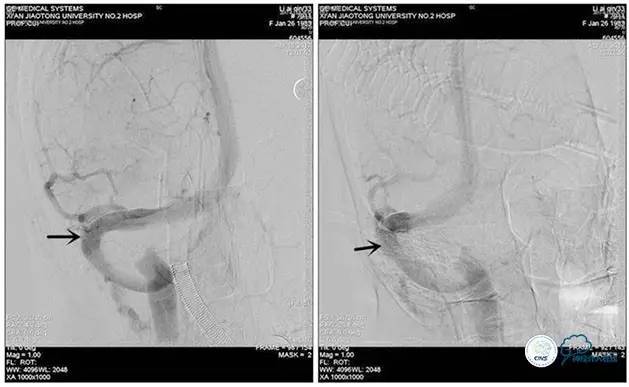

术中右侧ICA造影

右侧ICA斜位及窦内造影

右侧ICA斜位

窦内造影及路图

术中测压:

远端:520mmH2O,

近端:190mmH2O。

治疗方案:

1、8mm×40mm , EverCross球囊扩张;

2、8mm×40mm,Protégé自膨支架成形术。

术后右侧ICA造影

术后远、近端压力差为:0

术后右侧ICA斜位